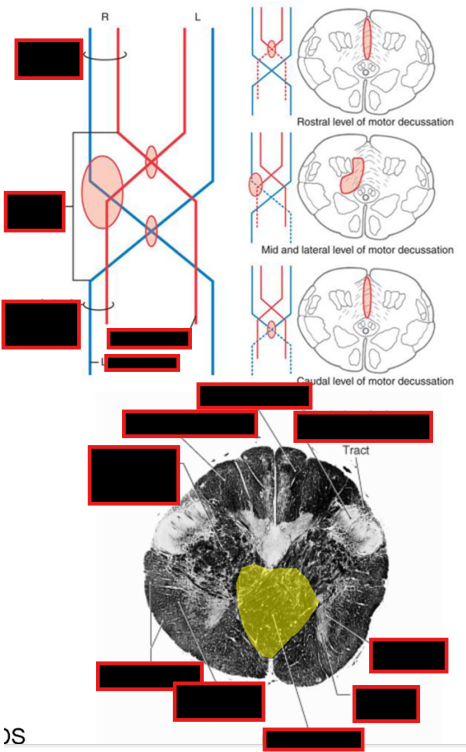

Describe the Pyramidal (Motor) Decussation

Location

Fiber Destiy

Somatotopy of Decussation

Location:

ventral surface of the medulla; disruption of the anterior median fissure

Fibers Destiny Here:

80-90 percent of corticospinal tract fibers decussates (L CST)

8% descend ipsilaterally → anterior funiculus → decussate segmentally (Anterior CST)

2% descend ipsilaterally to contribute to the lateral corticospinal tract (tract of Barnes)

Somatotopy of Decussation:

Upper Extremity fibers: Rostrally

Lower Extremity fibers: Caudally

THUS: iscrete lesions in the pyramidal decussation may produce different and somewhat unusual patterns of weakness.

@ level of pyramidal dessucation, What happen to these other tracts:

Medial Long. Fasciculus

Ant./Post. Spinocerebellar Tract

Anterolateral system (spinal lemniscus)

Rubrospinal tract

Other Tracts:

Medial Long. Fasciculus (descending limb - medial vestibulospinal tract) and Tectospinal Tract:

Pushed laterally by the decussating CST fibers.

Ant./Post. Spinocerebellar Tract:

Retain position similar to SC

medial to spinocerebellar tracts;

Retain position like SC

associated w/ ALS in caudal brainstem.

Retains similar position in the spinal cord.